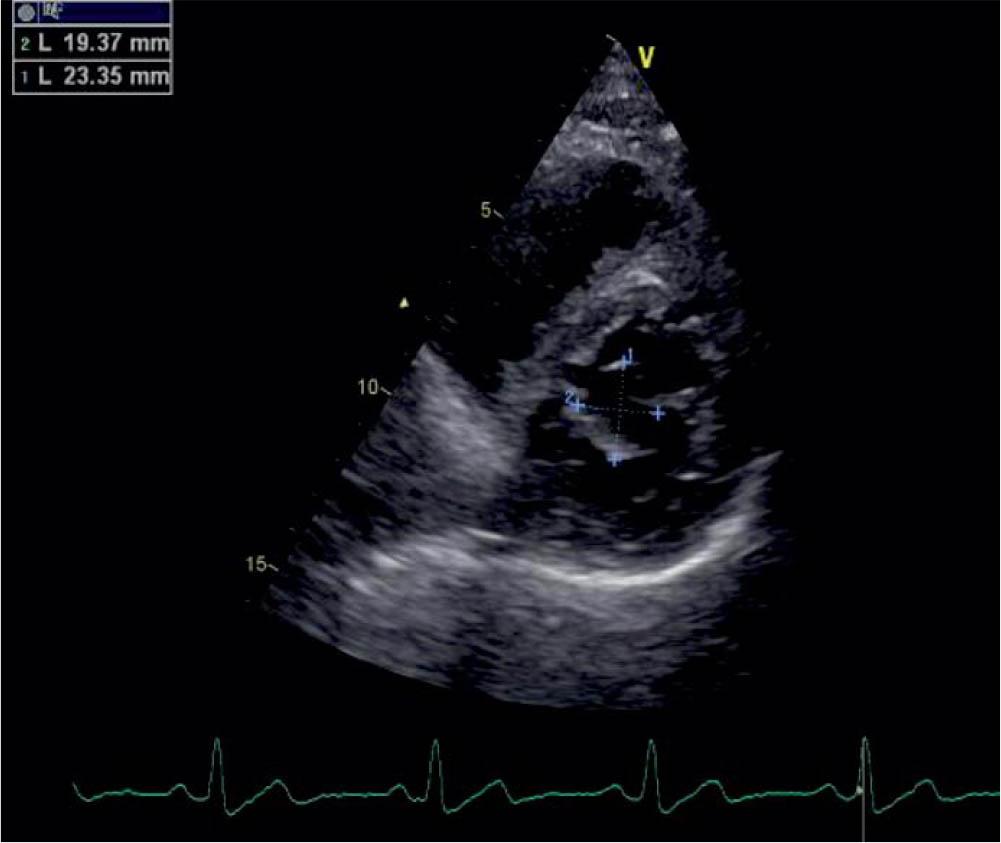

Figure 2

TTE parasternal short axis, visualization and measuring of the blood cyst.